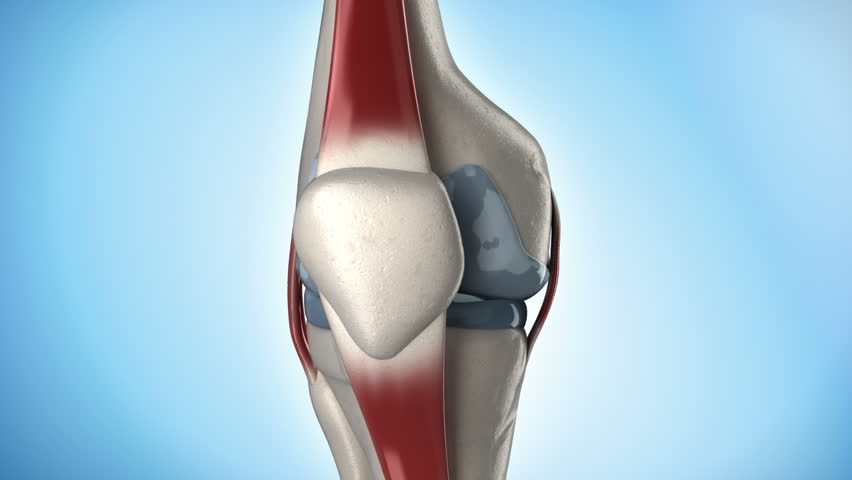

Ανατομία του γόνατος

Οι μηνίσκοι είναι σχήματος C, σφήνες ινώδους χόνδρου, που βρίσκονται μεταξύ του κνημιαίου πλακιδίου και των μηριαίων κονδύλων. Οι μηνίσκοι περιέχουν 70% κολλαγόνο τύπου I. Ο μεγαλύτερος μεσημβρινός  συνδέεται πιο σταθερά από τον χαλαρότερο, τον πιο κυκλικό πλευρικό μηνίσκο. Τα εμπρόσθια και οπίσθια κέρατα και των δύο  είναι ασφαλισμένα στα κνημιαία οροπέδια. Ο εγκάρσιος σύνδεσμος συνδέει τους δύο μηνίσκους. Ο οπίσθιος σύνδεσμος βοηθά στη σταθεροποίηση του οπίσθιου κέρατος του πλευρικού μηνίσκου στο μηριαίο κονδύλιο. Οι στεφανιαίοι σύνδεσμοι συνδέουν το περιφερικό χείλος χαλαρά με την κνήμη. Αν και ο πλευρικός συνδετικός σύνδεσμος περνάει πολύ κοντά, ο πλευρικός μηνίσκος δεν έχει καμία προσκόλληση σε αυτή τη δομή.

Η κοινή κάψουλα συνδέεται με ολόκληρη την περιφέρεια του κάθε μηνίσκου, αλλά προσκολλάται πιο σταθερά στο μέσο μηνίσκο. Μία διακοπή της προσάρτησης της αρθρικής κάψουλας στον πλευρικό μηνίσκο, που σχηματίζει το γειτονικό διάκενο, επιτρέπει στον τένοντα  να διέλθει στη θέση πρόσδεσής του στο μηριαίο σημείο. Η συστολή από τον τένοντα κατά τη διάρκεια της κάμψης του γόνατος τραβά τον πλευρικό μηνίσκο οπίσθια, αποφεύγοντας την παγίδευση μέσα στον χώρο των αρθρώσεων. Ο μεσαίος μηνίσκος δεν έχει άμεση μυϊκή σύνδεση. Ο μεσαίος μηνίσκος μπορεί να μετατοπιστεί μερικά χιλιοστά, ενώ ο λιγότερο σταθερός πλευρικός μηνίσκος μπορεί να κινηθεί τουλάχιστον 1 cm.

Οι ίνες κολλαγόνου των μηνίσκων προσανατολίζονται σε περιφερειακό μοτίβο. Όταν εφαρμόζεται μία δύναμη συμπίεσης στην άρθρωση του γόνατος, μεταδίδεται μία δύναμη εφελκυσμού. Το μηριαίο οστό προσπαθεί να θέσει τον ιστό σε επέκταση και μεσοπλαστική κάμψη.